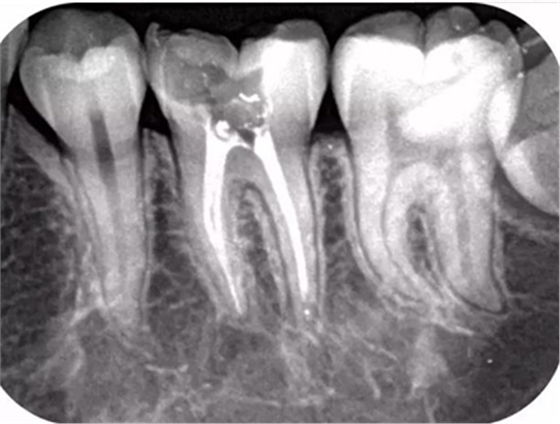

而本寶的拍照水平真是沒(méi)SEI了,高清X光影像,分辨率達(dá)12LP/MM,所有牙齒baby在我面前都是赤裸裸的,清晰到毫米以內(nèi)的異常都能捕捉得到。

(本寶拍的牙片,夠不夠赤果果)